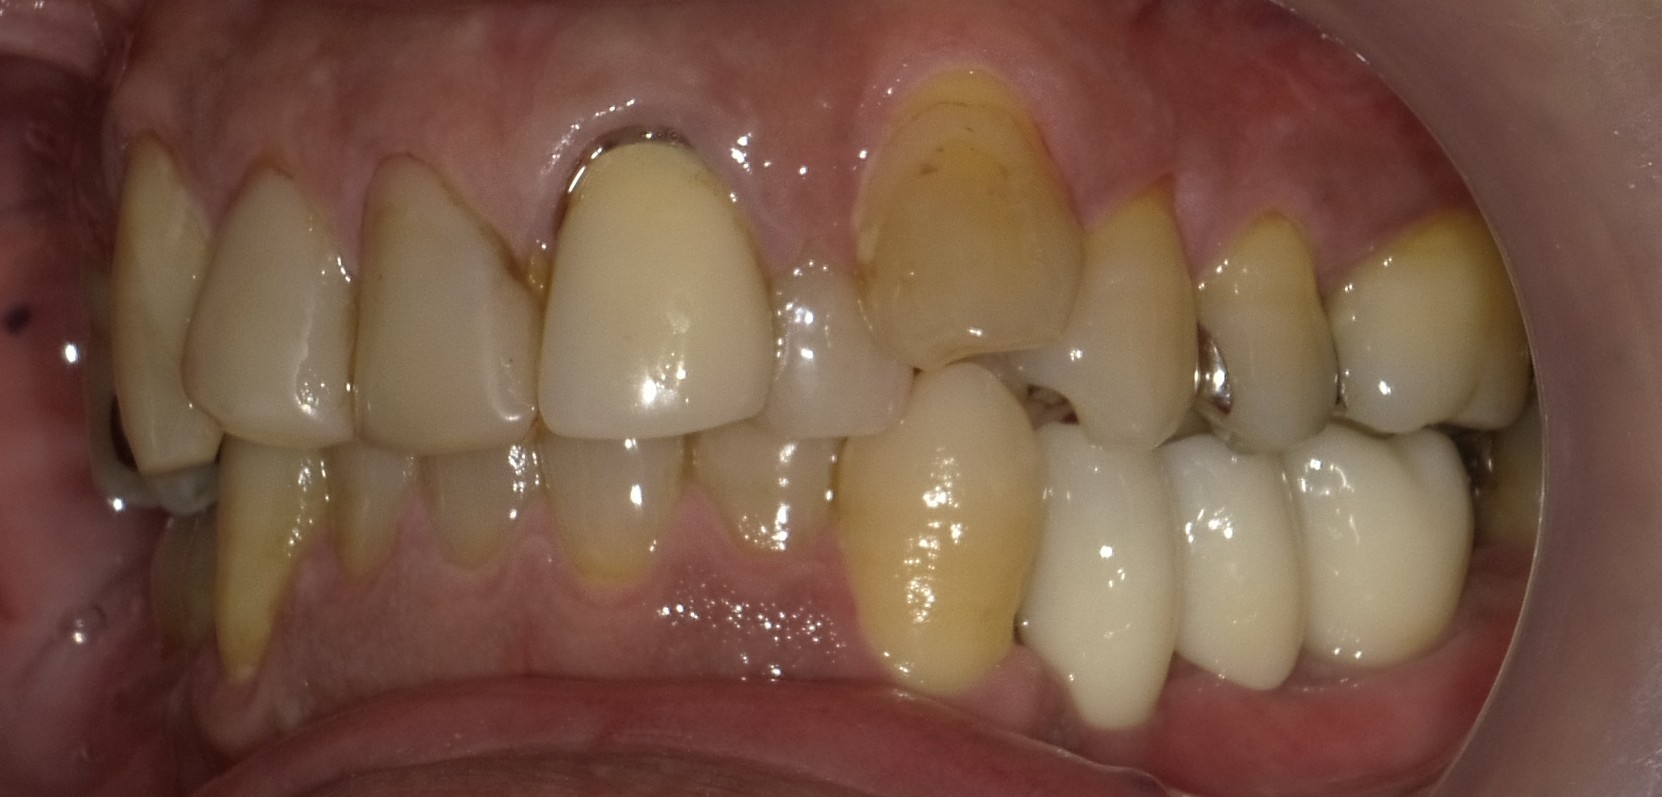

ブリッジの所がグラグラして 歯を抜くことになった 入れ歯は嫌だったのでインプラントにした 50代 男性ーインプラントー

ブリッジの所がグラグラして

歯を抜くことになった

入れ歯は嫌だったのでインプラントにした

インプラントは自分の歯のようでとても良い。